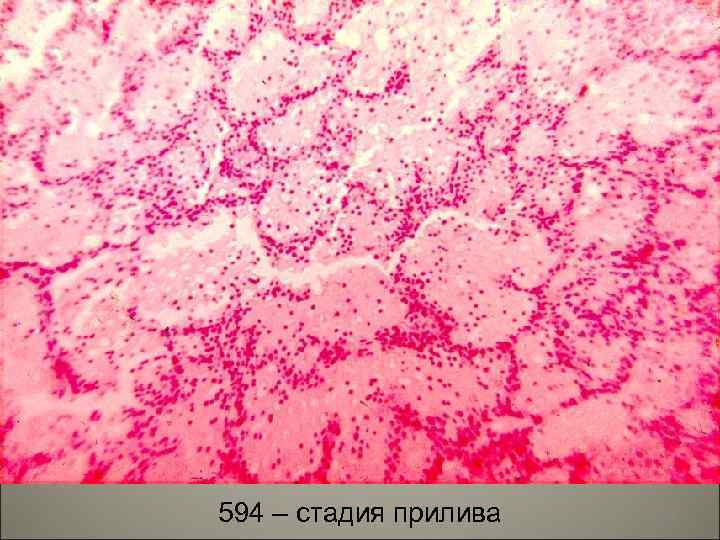

• Морфогенез. В классическом варианте в течение пневмонии последовательно проходят 4 стадии: прилива, красного опеченения, серого опеченения и разрешения. Все стадии занимают 9 -11 дней. 46

• I. Стадия прилива продолжается сутки, характерна резкая гиперемия и отек пораженной доли. В отечной жидкости много микроорганизмов. Ткань легкого имеет темно-красный цвет, который исчезает при надавливании. Патология захватывает целую долю, наблюдается подъем температуры, проливной пот. 47

594 – стадия прилива 48